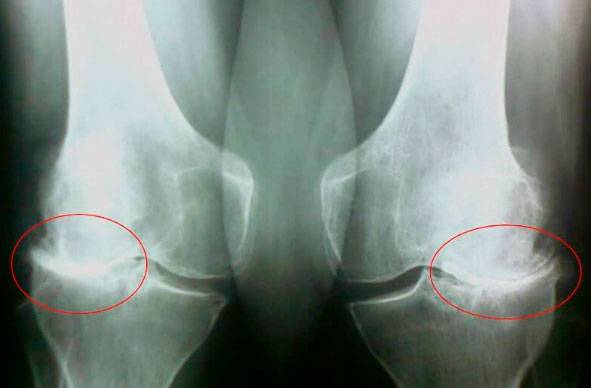

Podívejte se na tyto snímky, vidíte, že na pravém snímku chybí kloubní štěrbina, kosti se třou o sebe a způsobují silnou bolest. A tento proces je velmi obtížné zastavit! Za pár let bude člověk invalidní a nebude schopen se uživit.